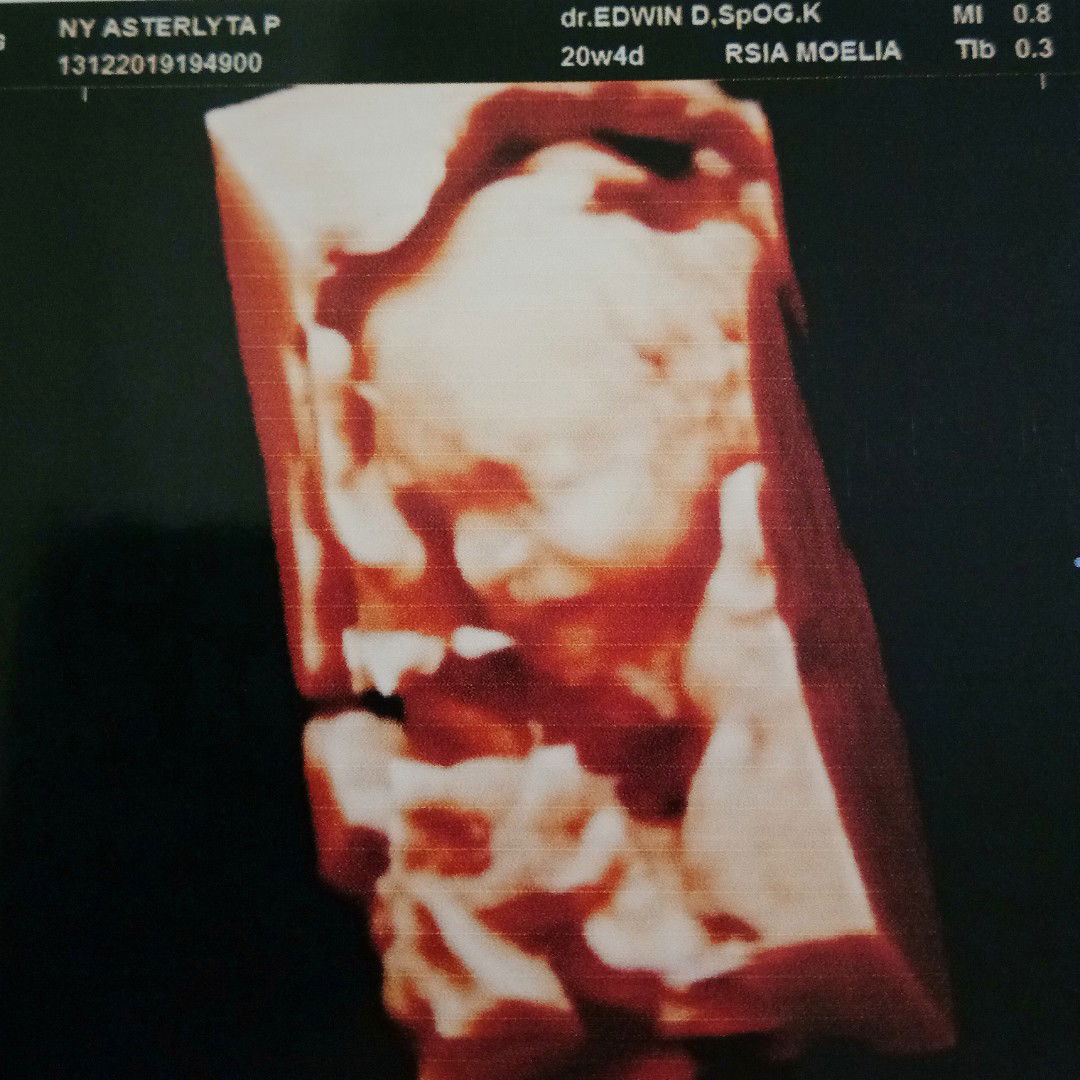

Halo bunda, ini USG anak pertamaku ke- 20 minggu. Banyak yang bilang kehamilanku perutnya kecil dll tapi aku bodo amat karena toh setiap diperiksa berat janinnya sesuai dengan usianya. Penting banget bagi bunda2 semua untuk paham kalau bentuk rahim kita beda-beda dan itu pula juga yang menentukan perut bunda kelihatan besar atau kecil. Jadi jangan khawatir bunda kalo ada yang bilang kecil perutnya. Yang penting dedek berkembang sehat! Ohya alhamdulillah anak pertamaku baby girl.. Hidungnya persis kayak bapaknya hehe. Gimana pengalaman bunda?#sharingiscaring :)